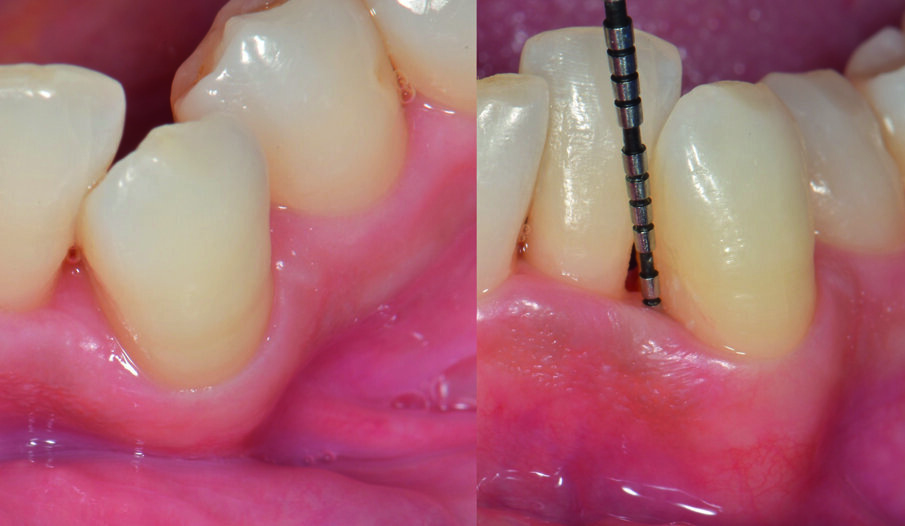

Fig. 4 - Sondaggio parodontale. PPD di 6 mm e CAL di 7 mm per l’elemento 33.

Fig. 5 - Fase di setting del prodotto H42. Il sito deve essere tenuto asciutto per 5 minuti dopo l’applicazione di H42 per favorirne l’adesione ai tessuti. Il prodotto è messo a colmare completamente la tasca, fino a uscirne.